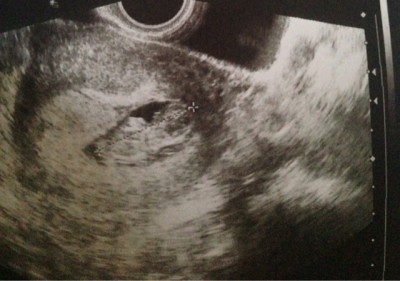

due cuoricini per i due fagiolini.